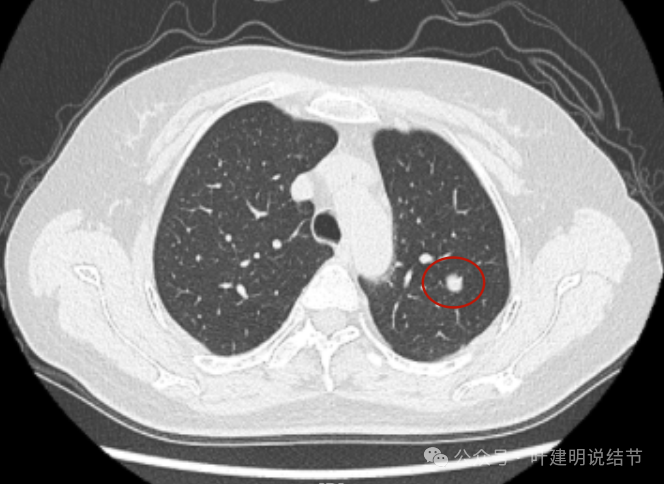

再来看2023年12月时连续层面的影像:

病灶出现,边缘区表面不是很光滑,似有少许磨玻璃成分以及边缘略显毛糙。

表面不是太光滑,中间的密度略显低。

血管贴得近,但没有牵拉或分支进入病灶,整体表面较为光滑。

与血管关系近,结节有膨胀感。

此层看与血管紧贴,没有间隙。局部有轻凹陷。

病灶明显感觉较为膨胀。

似见血管征,表面欠平滑,倾向浅分叶的样子。

边缘区密度不是太致密,有点像磨玻璃偏实的样子。

边缘区域混合密度的表现。